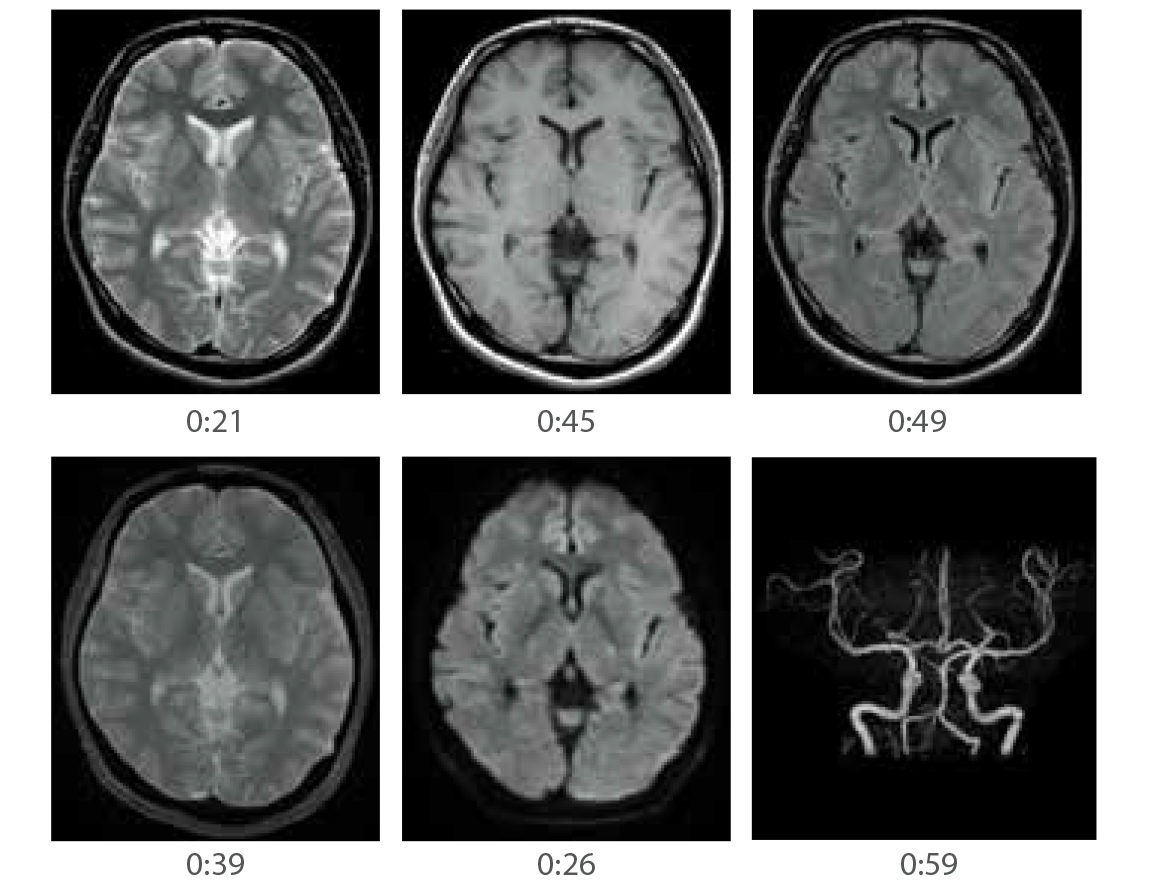

AutoPose is a slice line setting support function.

When the Scanogram imaging ends, the preset section is automatically set and can be registered up to five types of preset sections.

When AutoExam is executed, clipping is performed automatically after MRA imaging.

It is possible to perform additional clipping on images after automatic clipping.

OM-Line

MRA

without clipping

with AutoClip